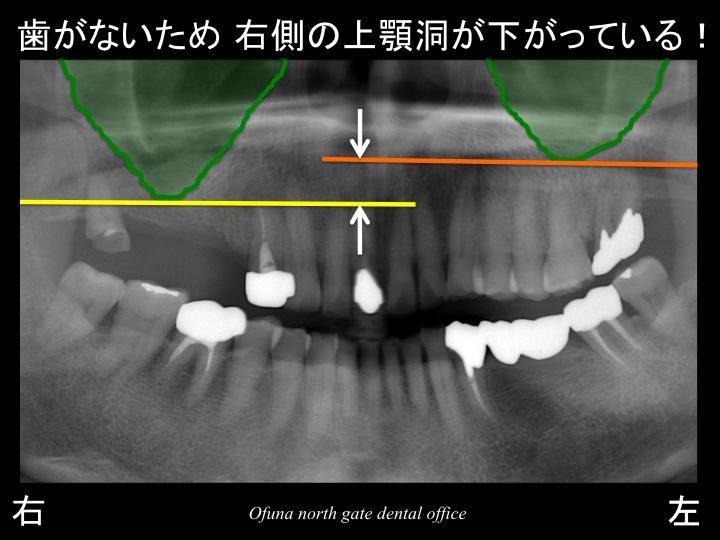

この右側の上顎洞は下方に下がってきたのです。

それを分かりやすくするために左側の上顎洞も一緒に表示してみましょう。

右側の上顎洞と左側の上顎洞では、その位置が違うのが分かるかと思います。

歯が欠存したために右側の上顎洞が下がってきたのです。

このように比較すると分かりやすいかと思います。

上顎が下がってくるのは、時間が経過すればするほど起こりやすくなってきます。

つまり、抜歯後はできるかぎり早急に対応しないとインプラント治療が難しくなるのです。